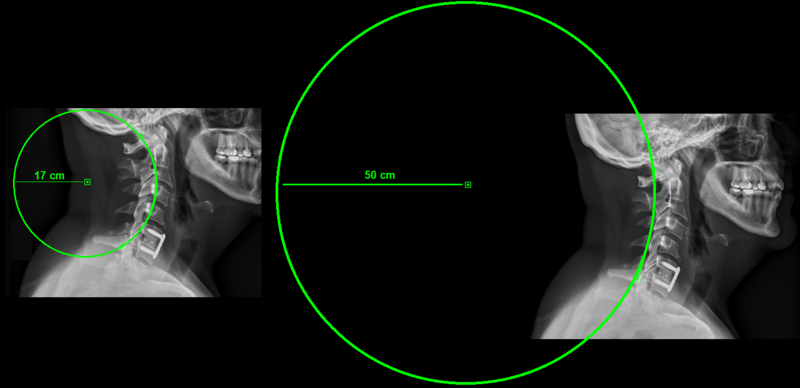

A curve will be drawn based on the radius of a circle including those points (default radius is 17cm):

To change the radius of the circle (curve):

1.      Click on the curve to activate it.

2.      Right click on it and a dropdown menu will appear. Choose “Change Curve Radius” to change the radius of the circle including the curve.

3.      Write the desired radius and then click ok.